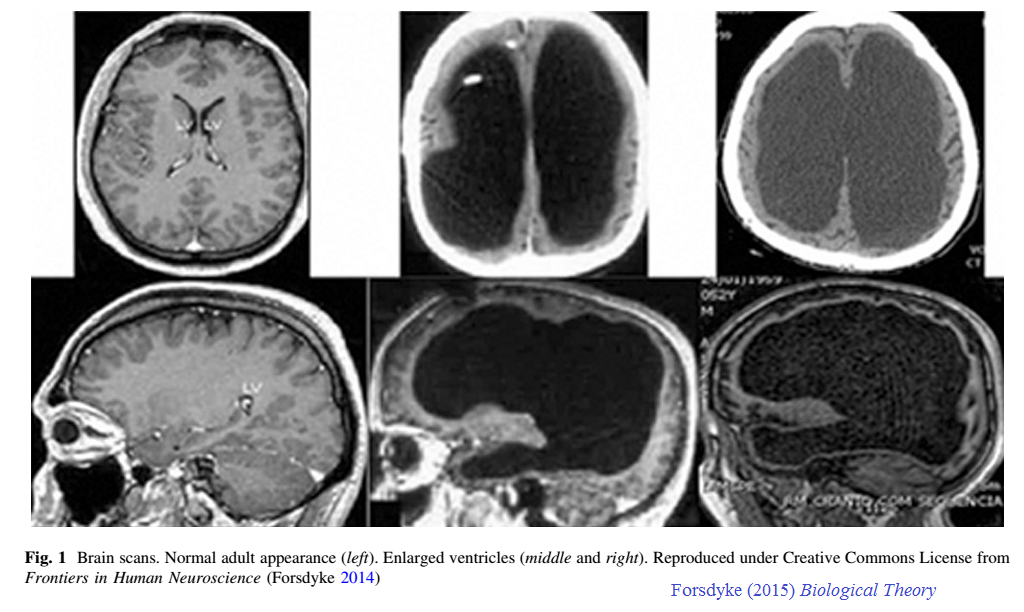

Nell'illustrazione di Forsdyke qui sotto il cervello adulto normale (a sinistra) è affiancato da due straordinari cervelli adulti post-idrocefalici. Gli spazi neri non sono altro che liquido cerebrospinale:

Questo fenomeno è stato notato dal pediatra inglese John Lorber che non ha mai pubblicato le sue osservazioni su una rivista scientifica, anche se è stato realizzato su di loro un documentario. Tuttavia, il suo lavoro è stato notoriamente discusso in Scienze nel 1980 da Lewin in un articolo intitolato "Il tuo cervello è davvero necessario?". C'è stato un certo numero di altri casi più recenti pubblicati.

Anche se gli enormi "buchi" in questi cervelli sembrano drammatici, la maggior parte della materia grigia della corteccia cerebrale, intorno alla parte esterna del cervello, sembra essere intatta e nel posto giusto; questo è visibile come 'corteccia' grigio scuro sotto il cranio. Ciò che sembra mancare è la sostanza bianca, l'insieme di vie nervose che collegano le varie parti della corteccia cerebrale l'una con l'altra, e con le altre aree del cervello.

Tuttavia, parte della sostanza bianca è ancora visibile come strato grigio chiaro che circonda i fori. La grande domanda è se questo strato di materia bianca è sufficiente a collegare la materia grigia e consentirgli di operare normalmente. Non sembra ce ne sia molta, ma d'altra parte, non sappiamo invero quanta materia bianca è strettamente necessaria.